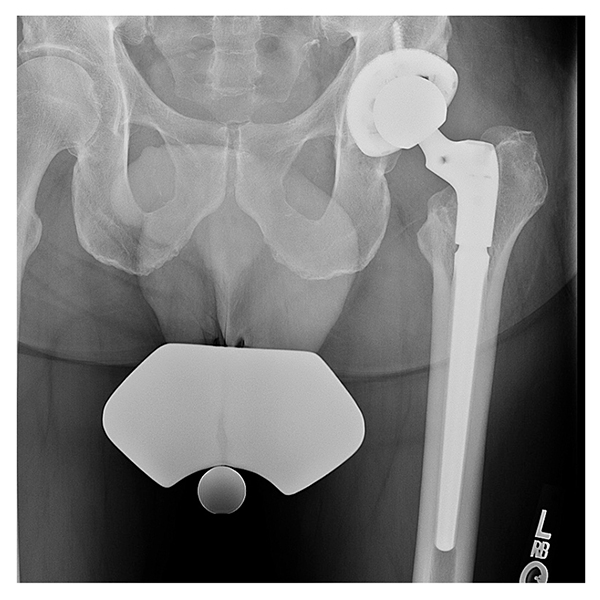

Although intraoperative cultures were negative, because of his history of positive intra-articular cultures for S. epidermidis and Escherichia coli, the patient received 6 weeks of IV vancomycin and cefepime. At the 6-week mark, both anterior and posterior incisions had healed, and the patient was compliant with 50% weight-bearing. When after a 2-week antibiotic holiday subsequent blood work and aspiration showed that the infection had resolved, the patient underwent reimplantation through the posterior approach with a revision acetabular component fixed with multiple screws and a diaphyseal engaging modular tapered stem (Fig. 3). It was noted that the anterior wall was deficient due to the underlying infection and explantation procedure. Intraoperative cultures were negative and postoperatively the patient was placed on a progressive weight-bearing routine with posterior precautions.

Figure 3: Postoperative radiograph demonstrating cementless revision involving a multihole acetabular cup with multiple screws and a modular tapered diaphyseal engaging stem.